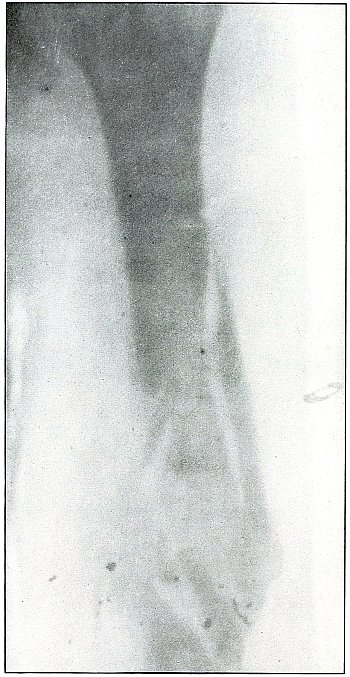

Plate 50.

[Pg 111]

Rifle—Plate 50.

LOWER EXTREMITY.

Gunshot Wound of the Right Thigh,

with Lodgment of the Bullet Behind the Femur.

There is no injury to the bone. The large diameter, shortened length,

and slight density of the shadow show the bullet to be some distance

from and inclining toward the plate and lodged in the muscles behind

the femur, nearer the side away from the photographic plate. It is

difficult to identify the right or left thigh from the radiograph, but

with the history of the wound in the right thigh and the outside of

the leg next to the plate the ball would lie nearer the inside than

the outside of the thigh, nearer the surface behind the femur. As the

shadow shows irregular outline and the location of the bullet low

velocity, the wound was caused by a ricochet shot at very long range.

The treatment is expectant and the course naturally favorable.